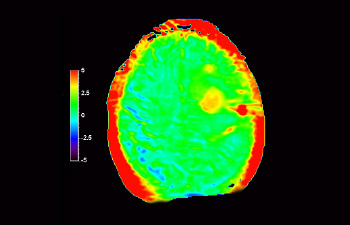

Brain with glioblastoma

3D APT

Enhanced diagnostic confidence in neuro oncology